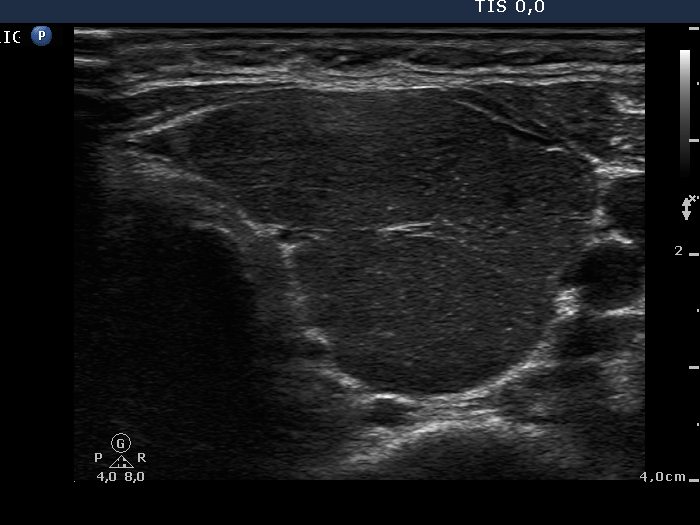

Palpation: diffusely enlarged thyroids.

Ultrasonography: A hypoechogenic, inhomogeneous thyroid was found with increased vascularization.